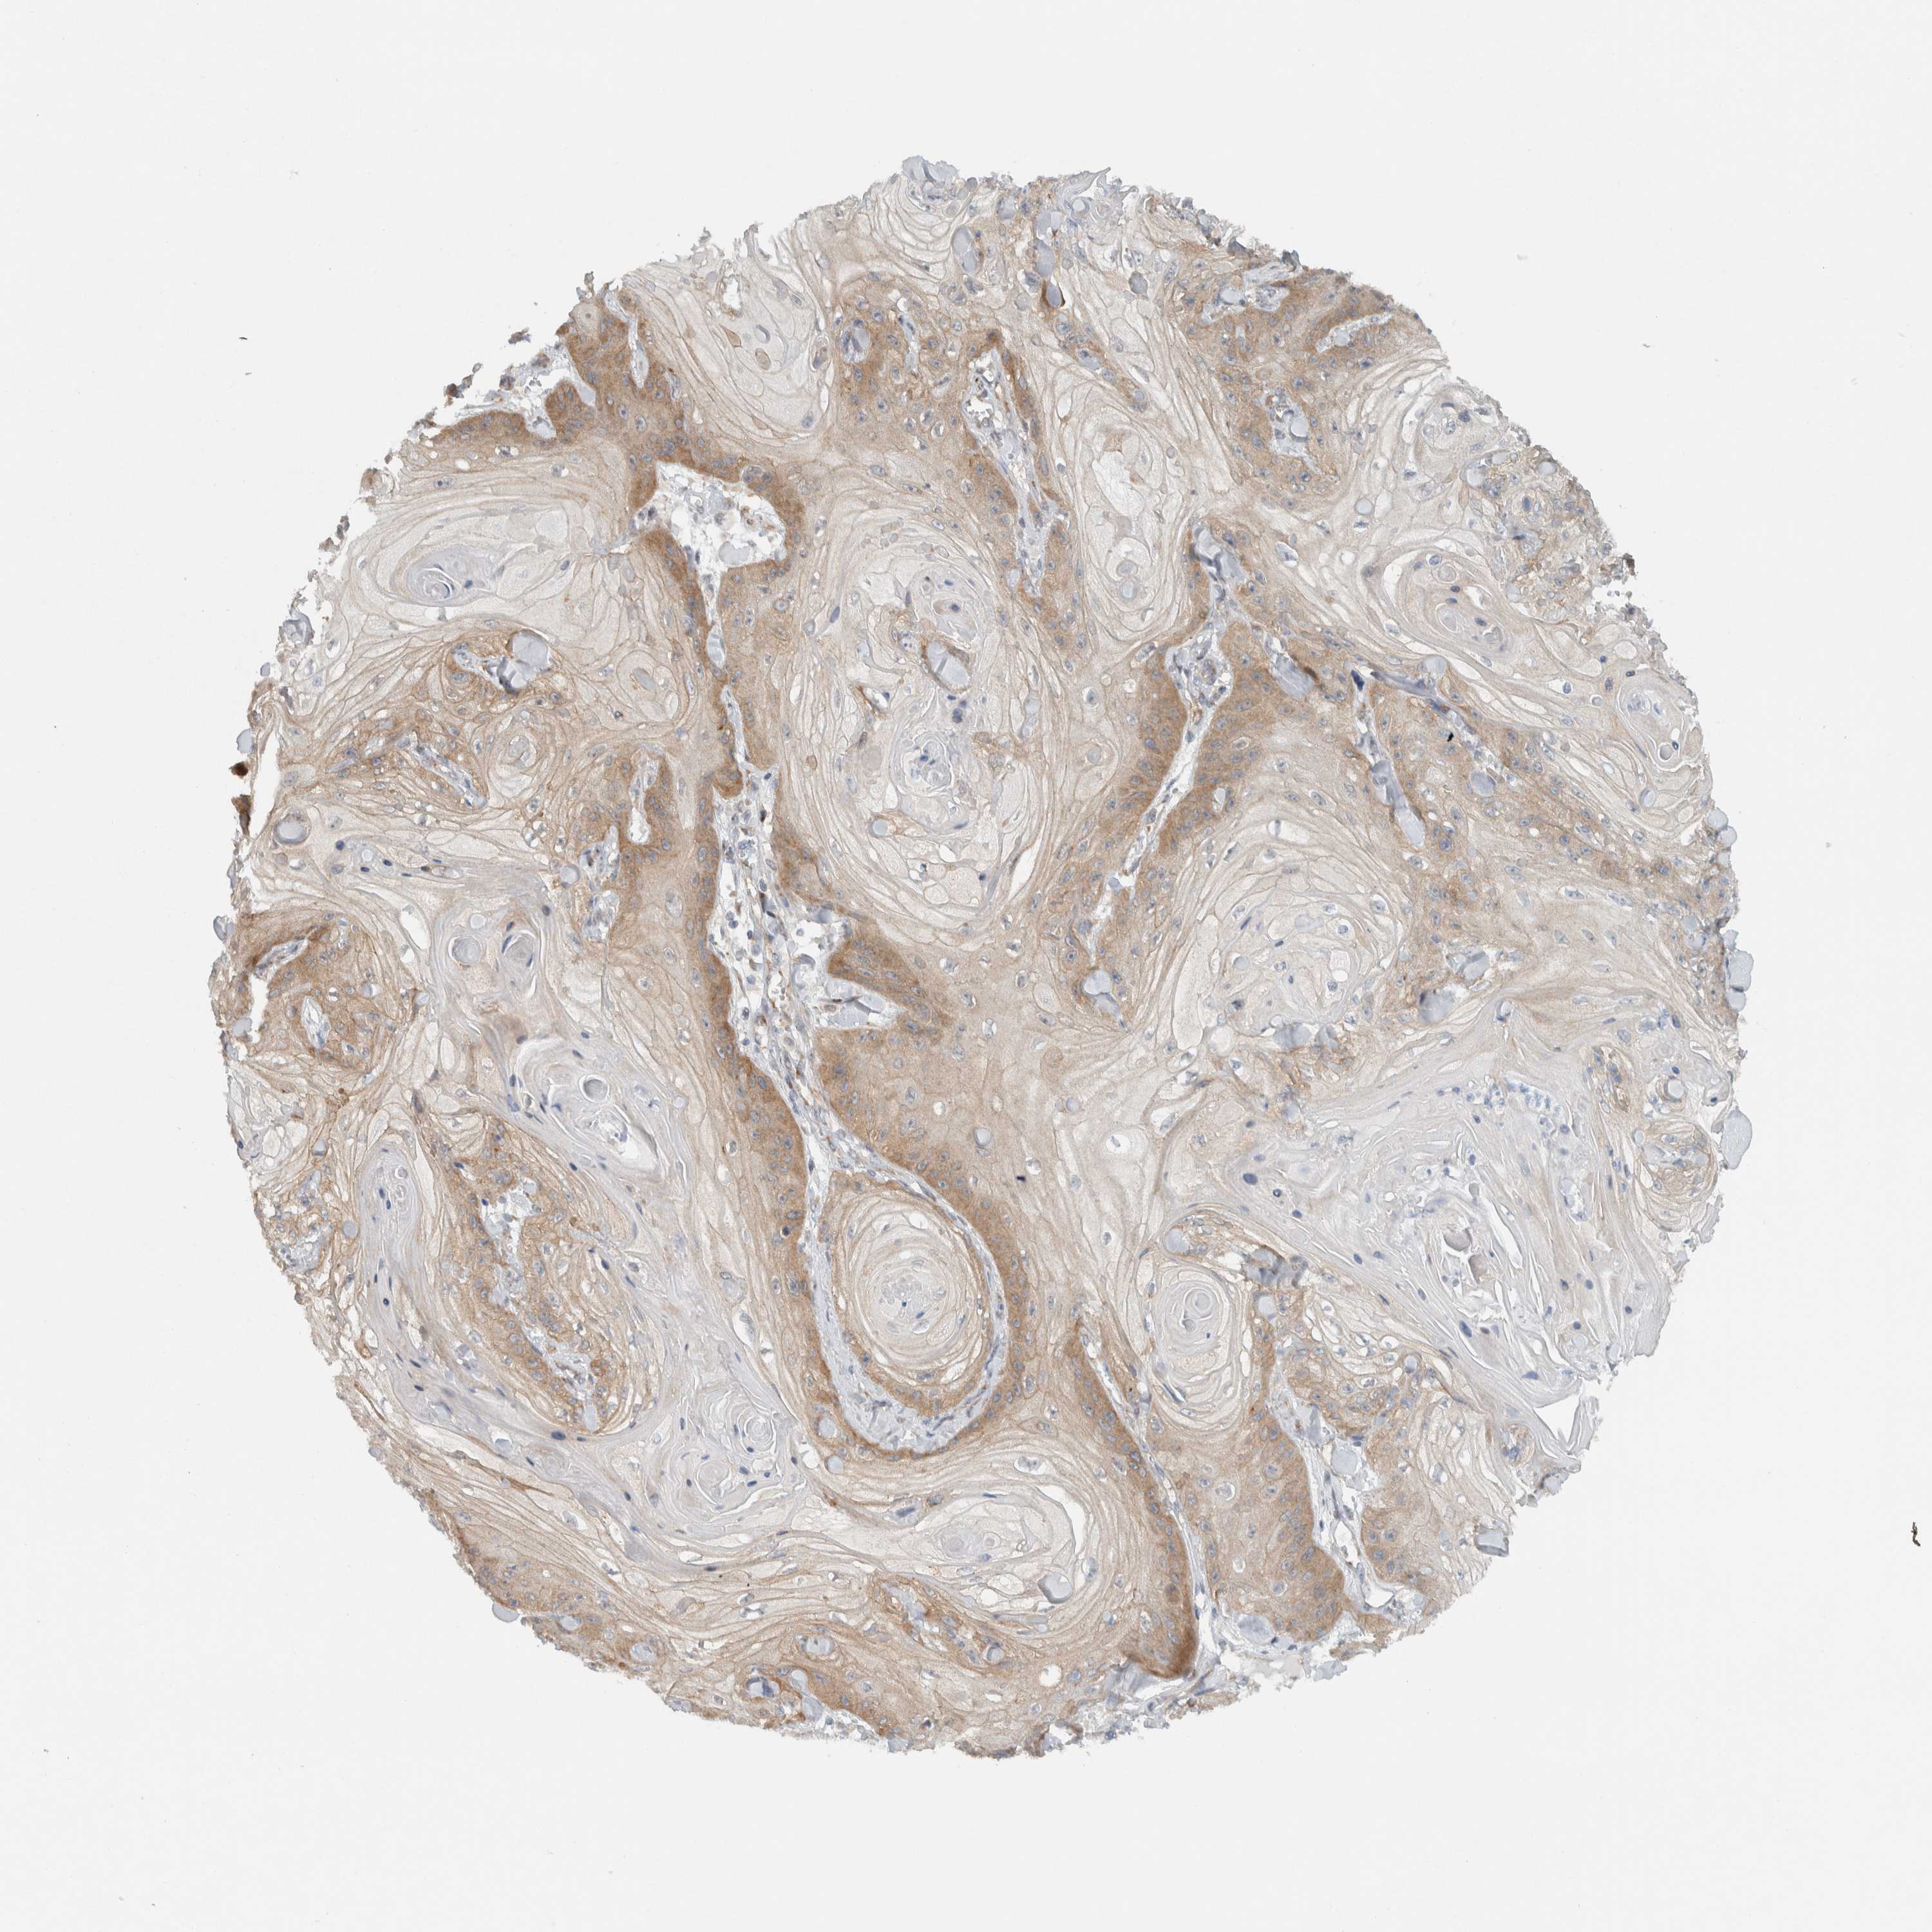

Basal cell and squamous cell cancer

SKIN CANCER - Protein expressioni

A mouse-over function shows sample information and annotation data. Click on an image to view it in a full screen mode. Samples can be filtered based on level of antibody staining by selecting one or several of the following categories: high, medium, low and not detected. The assay and annotation is described here.

Antibody stainingi

Antibody staining in the annotated cell types in the current human tissue is reported as not detected, low, medium, or high, based on conventional immunohistochemistry profiling in selected tissues. This score is based on the combination of the staining intensity and fraction of stained cells.

Each image is clickable and will lead to virtual microscopy that enables deeper exploration of all samples and also displays staining intensity scores, fraction scores and subcellular localization as well as patient and tissue information for each sample.

Antibody HPA024093

Staining

High

Medium

Low

Not detected

Intensity

Strong

Moderate

Weak

Negative

Quantity

>75%

75%-25%

<25%

None

Location

Nuclear

Cytoplasmic/membranous

Cytoplasmic/membranous,nuclear

Squamous cell carcinoma, metastatic, NOS